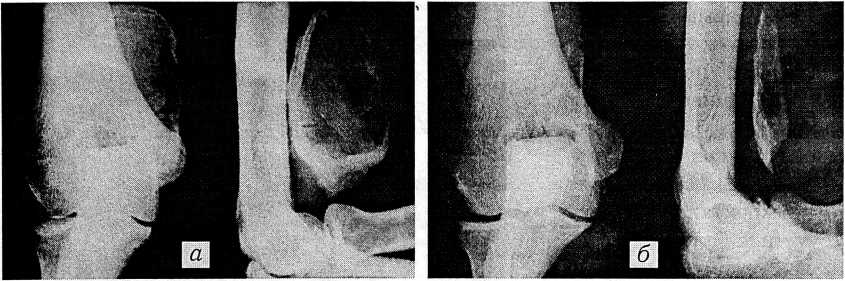

Рис. 1. Болезнь Легга—Калве—Пертеса: а — до лечения; б — через 3 мес после 40-дневного лечения магнитофором.

По поводу микротравматических заболеваний* МП лечились 115 детей в возрасте от 3 до 16 лет. Из них болезнью Шейермана страдали 5, болезнью Кинбека — 2, болезнью Легга—Калве—Пертеса — 76, болезнью Кенига — 1, болезнью Осгуда—Шлаттера — 12, остеохондритом бугра пяточной кости — 16, болезнью Келера II — 3 ребенка. Наибольший интерес представляет группа из 76 детей с болезнью Легга—Калве—Пертеса. Все они в течение 40 дней лечились магнитофорами площадью 16 см2, наложенными на область бедренного треугольника. У 35 детей, лечение которых было начато до возникновения импрессионного перелома эпифиза головки бедренной кости, наступило полное выздоровление (рис. 1).

При начале магнитотерапии уже после редукции высоты головки у 38 из 41 ребенка получено значительное улучшение (увеличение высоты головки на контрольной рентгенограмме при отсутствии клинических признаков болезни), у 3 детей улучшения не отмечено. Отдаленные рентгенологические результаты были лучше непосредственных.